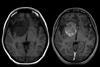

NewsCD47 protein found to drive glioblastoma growth

University of Adelaide researchers have discovered that CD47, a protein known for helping cancer cells evade immune detection, also directly promotes glioblastoma growth and invasion through a novel molecular pathway involving ROBO2 stabilisation.